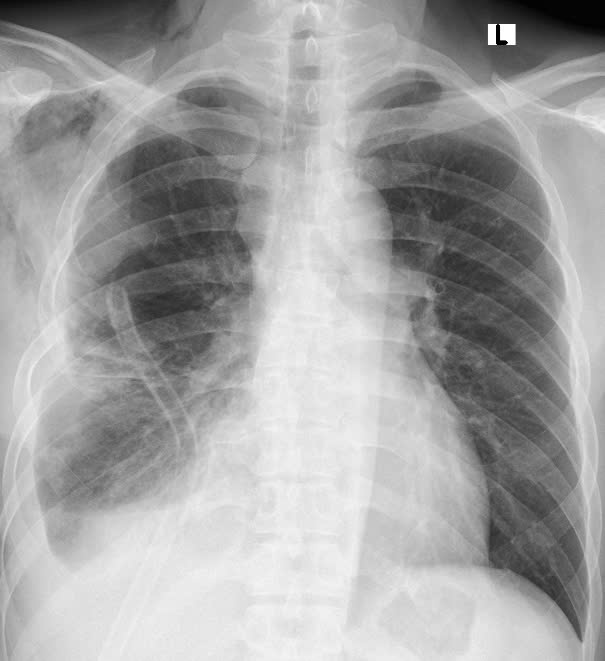

Hình ảnh phim chụp X.quang trước và sau khi phẫu thuật. Hình trước phẫu thuật (bên trái): Khối u xâm chiếm khoang ngực, gây xẹp gần như toàn bộ phổi phải

“Trong quá trình phẫu tích, khối u dính chặt vào mạch máu trung thất, có vỏ mềm và tăng sinh nhiều mạch máu gây chảy máu ồ ạt. Ê kíp đã có sự chuẩn bị từ trước, xác định ca mổ có nguy cơ chảy nhiều máu, bệnh nhân được chuẩn bị sẵn sàng máu để truyền. Trong mổ bệnh nhân được truyền bù 02 đơn vị máu, đồng thời ê kíp nhanh chóng kiểm soát tình hình bằng kỹ thuật kiểm soát cuống mạch nuôi khối u và khâu buộc thắt mạch cầm máu. Việc tiếp cận và bóc tách đòi hỏi độ chính xác tuyệt đối để tránh tổn thương các cơ quan quan trọng như tim, phổi và mạch máu lớn. Sau 02 giờ căng thẳng, khối u khổng lồ đã được lấy trọn vẹn ra ngoài, phổi phải giãn nở trở lại, hồi phục hình thái và chức năng bình thường”, TS.BS. Ngô Gia Khánh – Trưởng khoa Phẫu thuật Lồng ngực và Mạch máu chia sẻ.

Chỉ một ngày sau mổ, bệnh nhân đã có thể ngồi dậy, đi lại nhẹ nhàng và xuất viện sau 4 ngày trong trạng thái khỏe mạnh, nhẹ nhõm. “Tôi có cảm giác như được sống lại lần thứ hai. Cảm ơn các bác sĩ của Bệnh viện Bạch Mai đã mang lại cho tôi một cuộc đời mới”, bệnh nhân xúc động nói.